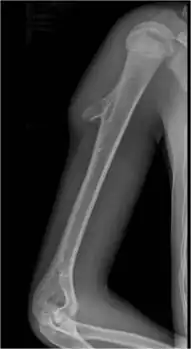

| Cancerous (Chondrosarcoma) | Conventional chondrosarcoma grade I (axial skeleton)-III[1][2] | ![]() |